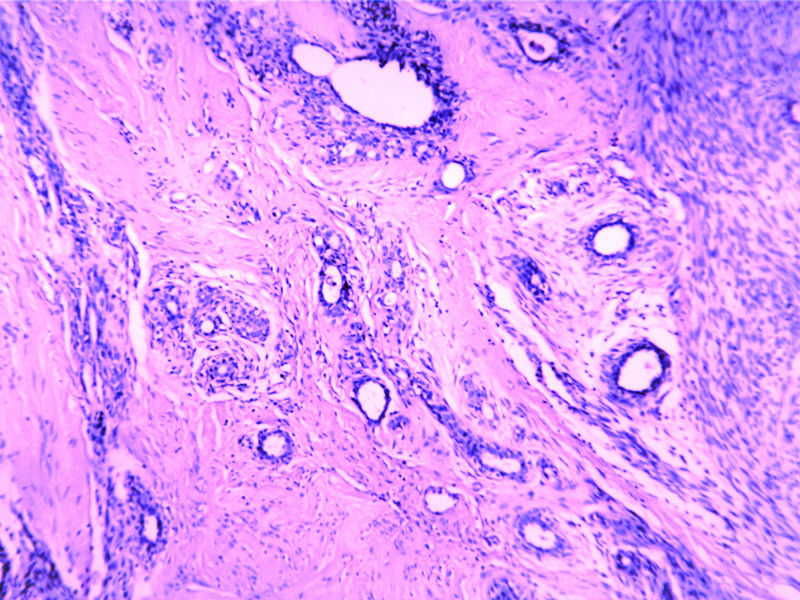

B3817

包块-有包膜(V3x3x2,39y)

图2

叶状肿瘤 导管周间质肿瘤